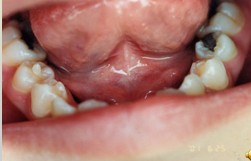

解析: 缺额牙

缺额牙-个别牙缺失:部分牙缺失的病因尚不明确。牙板生成不足或牙胚增殖受抑制;遗传、家族性。临床表现包括:缺失数目1至数颗;乳恒牙列均可发生,恒牙先天缺失常见,发生率2.3%-9.6%;好发缺失的牙位:下第二双尖牙、上侧切和上第二双尖牙,单侧或双侧;乳牙先天缺失与恒牙缺失有关。其治疗包括:恢复咀嚼 保持良好合关系:缺失少,对牙列、咀嚼、美观影响不大的不治疗。活动义齿修复,每年更换一次。

解析: 先天性无牙畸形 Total Anodontia

先天性无牙畸形的病因:外胚叶发育不全综合症、遗传性疾病。其临床表现:无汗、少汗、毛发稀疏、乳恒牙均可缺失、牙齿稀疏、牙形小、圆锥状。治疗:活动义齿修复。